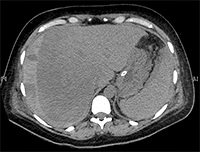

Liver diseases in pregnancy are rare. They are divided into pregnancy-related diseases, i.e., induced by pregnancy, and pregnancy-independent diseases, occurring as standalone conditions [2].<br />In addition to HELLP syndrome, pregnancy-related diseases include: hyperemesis gravidarum, intrahepatic cholestasis of pregnancy, preeclampsia and eclampsia, and acute fatty liver atrophy. These conditions affect and complicate approximately 5.5% to 13.5% of pregnancies. Preeclampsia, eclampsia, HELLP syndrome, and their complications, such as hepatic infarction and liver rupture/hematoma, are associated with hypertension in pregnancy. The most common conditions are preeclampsia and eclampsia, which affect 5-10% of pregnancies, and approximately 5% to 10% of these develop HELLP syndrome [3-5]. It is estimated to occur in approximately 6 pregnant women per 1000 pregnancies [2].<br />The concept and creation of the acronym HELLP (H = hemolysis, EL = increased liver enzyme levels in the blood, LP = decreased platelet levels) was introduced by Louis Weinstein, who in 1982 presented the results of an analysis of a group of pregnant women with highly pronounced consequences of preeclampsia and eclampsia [2,6]. The researcher showed that all patients had hemolytic anemia associated with microangiopathy, changes in the shape of erythrocytes in the peripheral smear, moderate to severe thrombocytopenia, and abnormal enzymatic tests of liver function, usually in combination with epigastric pain, nausea and vomiting, and severe hypertension and proteinuria often coexisted with these symptoms [3,6]. Since the publication of L. Weinstein's work, others have made significant research contributions to understanding the pathogenesis, natural history, clinical spectrum, classification, and management strategies for this syndrome [3].<br />HELLP syndrome typically develops suddenly in the 2nd or 3rd trimester of pregnancy or within 48 hours of delivery [5,7,8]. It usually accompanies preeclampsia/eclampsia, but can also occur independently. As in the aforementioned conditions, the likely cause of the syndrome is abnormal placental development and ischemia, which induce oxidative stress, resulting in the release of factors that systematically damage the vascular endothelium through platelet activation, vasoconstriction, and loss of the typical pregnancy-related relaxation of vascular smooth muscle [3,9-13].<br />The liver plays a central role in the pathogenesis of HELLP syndrome and is key to understanding the nature of the disorder. Dysfunction and death of perihepatic hepatocytes in a given patient likely correlates with the severity of the condition. The previously discovered CD95 protein (APO-1, FAS), which plays an important role in the pathogenesis of liver disease, mediates hepatocyte apoptosis by binding to Fas-ligand protein (a ligand for the Fas receptor), a member of the TNF receptor family. Fas-ligand is produced by the placenta, and its serum levels increase during the course of the disease and correlate with its severity. Blocking CD95 signaling reduces serum hepatocytotoxic activity in HELLP syndrome [15].<br />This model of HELLP syndrome pathophysiology has been confirmed by other studies, demonstrating that the liver is the target and the placenta is the initiator of the disorders [3].<br />Many authors emphasize the similarity of HELLP syndrome to the Systemic Inflammatory Response Syndrome (SIRS), which may be evidenced by high levels of inflammatory mediators in serum and liver tissues and clinically available laboratory parameters such as the level of leukocytosis, which increases proportionally to the advancement of the disease [15-17].<br />Currently, there are two basic laboratory classification systems for HELLP syndrome: Mississippi and Tennessee, which were created for the purposes of diagnosis, assessment of disease advancement, and evaluation of treatment efficacy [2,3]. Considered separately, they also provide a platform for comparison of research results. They were developed in the 1980s at the research centers of the Universities of Tennessee and Mississippi.<br />The Mississippi classification takes into account the values of three basic parameters measured in blood serum: platelets, liver enzymes - AST and ALAT, and lactate dehydrogenase - LDH, which correlates with the intensity of hemolysis. Classification is ultimately determined by the lowest platelet count in the course of the disease. Grade 1 is associated with the most severe form of the disease, and grade 3 with the mildest. In this classification, all three parameters must be abnormal to diagnose HELLP syndrome.<br /><br />Mississippi Classification:<br />1. Platelet count 50,000, AST and/or ALAT 70 IU/L, LDH 600 IU/L<br />2. Platelet count 100,000, AST and/or ALAT 70 IU/L, LDH 600 IU/L<br />3. Platelet count 150,000, AST and/or ALAT 40 IU/L, LDH 600 IU/L<br /><br />The second classification system that has become common is the Tennessee classification. It defines the so-called true (complete) and incomplete (partial) HELLP syndrome.<br /><br />Tennessee classification:<br />1. Complete HELLP syndrome: platelet count 100,000, AST 70 IU/L; LDH 600 IU/L or bilirubin 1.2 mg/% and abnormal erythrocyte count